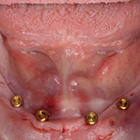

新たな歯根破折歯の対応としての

Nd:YAGレーザー照射